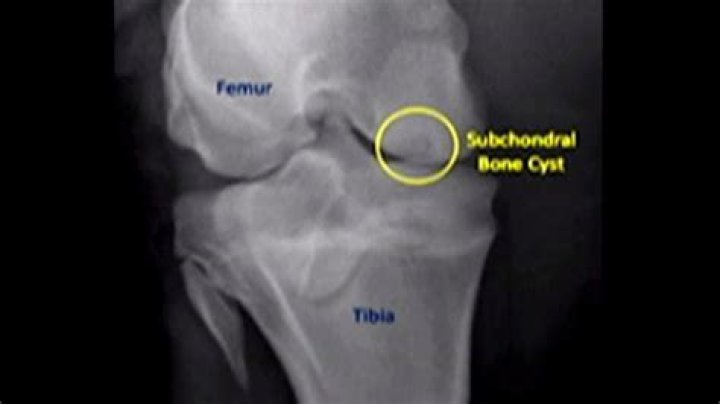

Why do subchondral cysts form?

A subchondral cyst is a fluid-filled space inside a joint that extends from one of the bones that forms the joint. This type of bone cyst is caused by osteoarthritis. It may require aspiration (drawing the fluid out), but the arthritis condition usually must also be addressed to prevent further cyst formation.

Histopathology Bone--Osteoarthritis, subchondral cyst

What causes bone cysts in knee?

Causes of Subchondral Bone Cysts

Osteoarthritis (OA) is the most common. It breaks down the cartilage. OA can happen from simple wear and tear over time, or because of a sudden injury to a joint. Either way, the normal, smooth, gliding of one bone against another in your joints starts to cause more friction.

A subchondral bone cyst (SBC) is a fluid-filled sac that forms in the bone just beneath the cartilage of a joint, such as the hip, knee, or shoulder. These cysts can develop in people with osteoarthritis and are usually not treated.